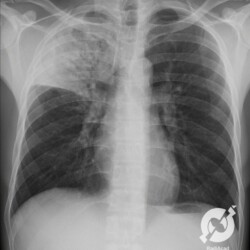

E o nome dado a esta alteração radiográfica que corresponde à substituição do ar alveolar por líquido é a consolidação alveolar.

Uma consolidação alveolar é, por definição, uma opacidade (imagem densa, branquinha) homogênea ou às vezes heterogênea (pela presença de calcificações ou cavidades), de limites mal definidos, exceto quando toca a pleura da parede ou das cissuras pulmonares. É um termo usado tanto em radiografia, como em tomografia computadorizada. Na tomografia, um outro termo é usado: vidro fosco, que é uma opacidade (branquinha mas não tanto como a consolidação), que borra o pulmão mas deixa ver os vasos de permeio (igual bigode de adolescente: dá pra ver todo o fundo).

Nós vamos mostrar aqui um pequeno apanhado de pneumonias de variados agentes, em diversos segmentos e lobos pulmonares, com extensões variadas. O objetivo é identificar o padrão radiológico de consolidação alveolar e não determinar o agente infeccioso, isso vai ser assunto para mais adiante. Aliás já antecipo que é fundamental saber localizar a lesão, porque alguns destes bichos gostam de determinados segmentos, alguns tumores também têm as suas preferências, então localização é fundamental. Se localização não fosse importante, um apartamento na beira do mar sairia o mesmo preço de um apartamento de frente pra BR-101, concordam?

Seguem alguns dos nossos casos de pneumonia para vocês treinarem os olhos e não se apavorarem nos plantões.